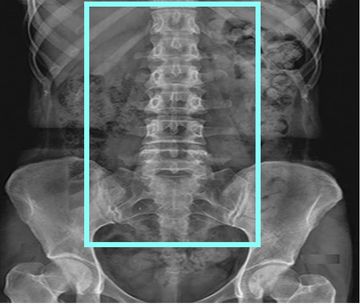

Helical Supine

2.5x2.0 GE bone/2.0x2.0 Siemens bone 2000W 500L

2.5x2.0 Ge standard / 2.0x2.0 Siemens standard 400W 40L

0.625x0.625 GE bone and standard / 0.75x0.7 Siemens bone and standard

Reformats:

coronal 1.25x1mm GE bone and std

coronal 1.5x1.0 Siemens bone and std

sagittal 1.25x1.0 GE bone and std

sagittal 1.5x1.0 Siemens bone and std

angled reformats through each disc space 1mm 15 FOV standard algorithm (if ordered)

VRT rotate and tumble every 10 degrees (If ordered or hardware is present)